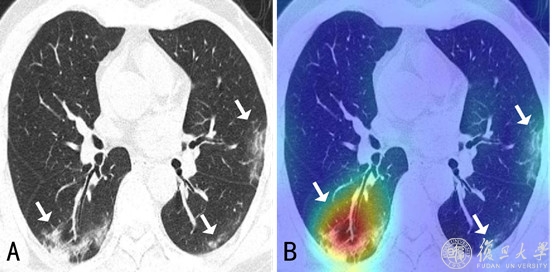

CT影像和算法模型检测后的可视化结果(演示区域存在病灶)

新型冠状病毒引起的肺炎,与其他病毒性肺炎、细菌性肺炎在CT影像呈现上有诸多相似之处。三种肺炎都存在视觉相似的病灶(如磨玻璃影),目前临床发现可适当利用病灶在肺部空间的分布等更多差异信息进行区分。

“现阶段医生需要在大量的影像数据中快速诊断出新冠肺炎的病例,此外还需要诊断出病灶分布的位置、大小等来评估严重程度。”薛向阳介绍,针对临床的现实需求,团队将设计目标定位于“肺炎分类鉴别”和“关键病灶检测”两大功能,前者是为区别健康状态、新冠肺炎、其他病毒性肺炎、细菌性肺炎,后者则为找到并分隔出磨玻璃影等病灶区域。